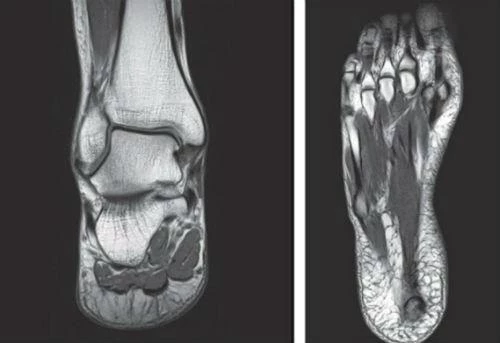

В ходе исследования авторы отобрали семь человек с различной подвижностью свода стопы. Испытуемых просили ходить и бегать как обычно, в то время как их ноги снимали на высокоскоростные рентгеновские камеры. Параллельно проводили замеры высоты свода стопы. Применялся и метод компьютерной томографии.